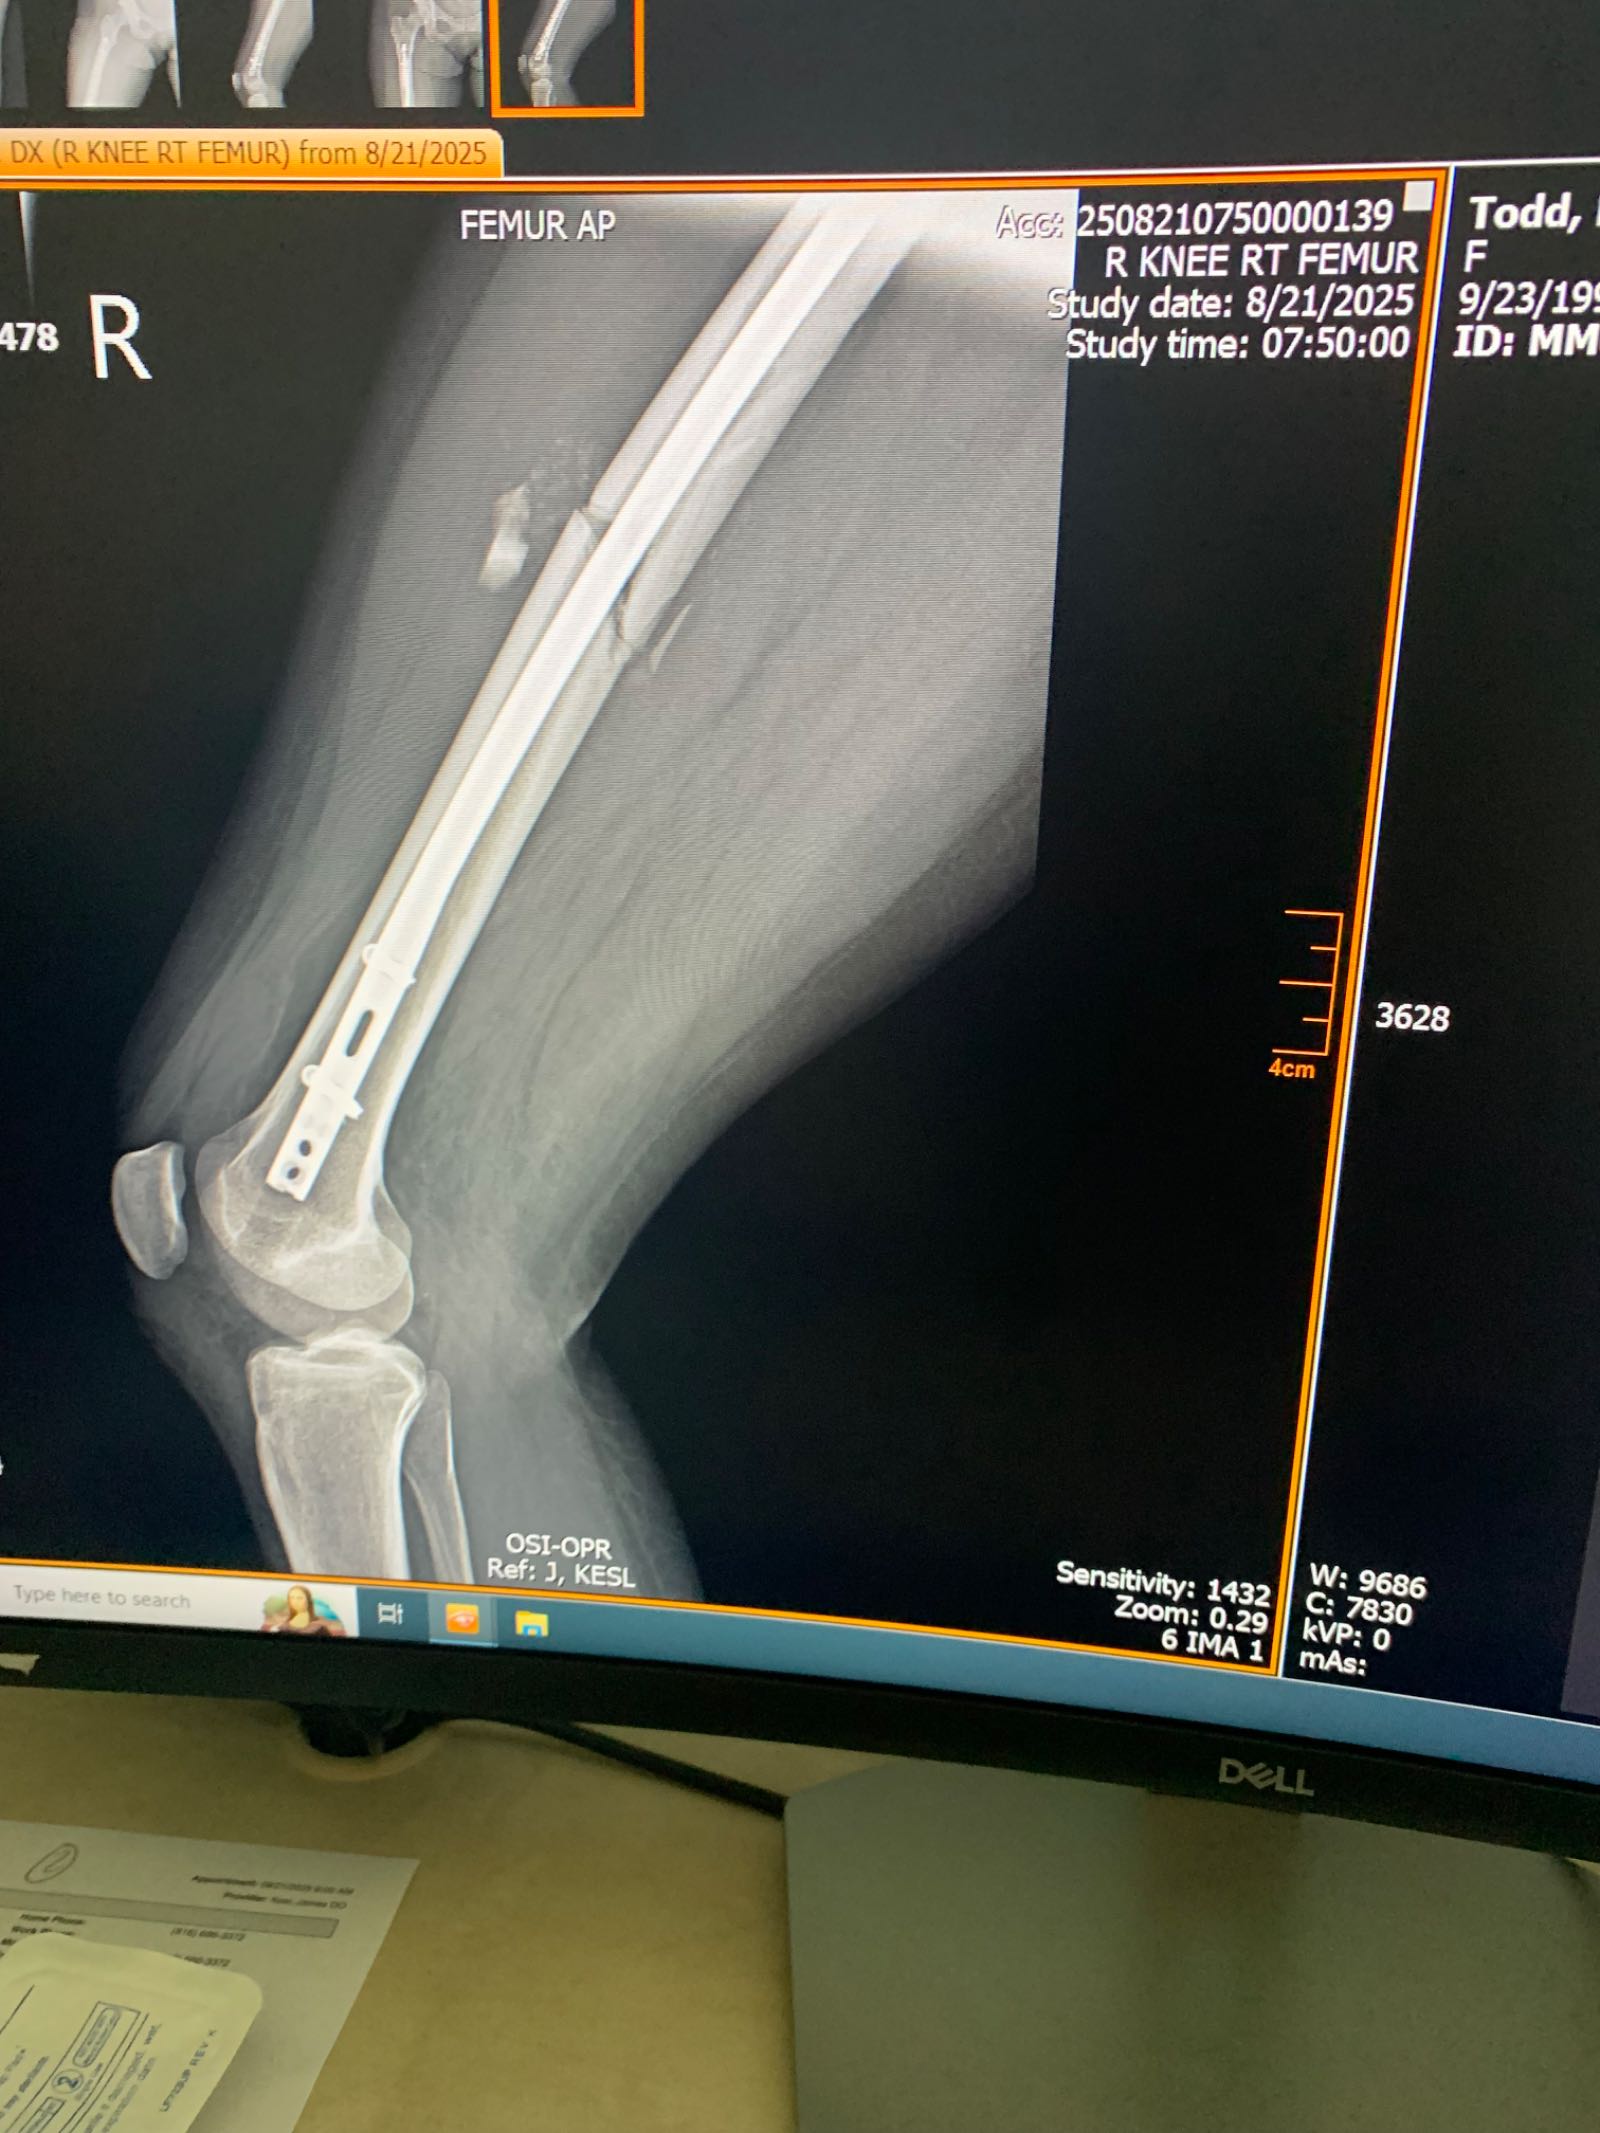

Life can change in an instant. I never imagined how fortunate I was to survive until I saw the wreckage of my car. The memory of the accident has vanished, replaced only by the reality of my injuries—a broken femur, a large head wound, and a daunting path to recovery ahead. As I navigate this journey of learning to walk again, the strength and love of my two children are my guiding lights. They need their mom back to normal, and your support could be the beacon that guides us through this difficult time. The medical bills are mounting, and being out of work has placed a heavy burden on our family's shoulders. Your generous donation will help cover these expenses, allowing me to focus on healing and returning to the mom my kids know and love. Please consider making a donation today. Every contribution, no matter how small, brings us closer to recovery and brighter tomorrows. From the bottom of our hearts, thank you for your kindness and support during this challenging time.